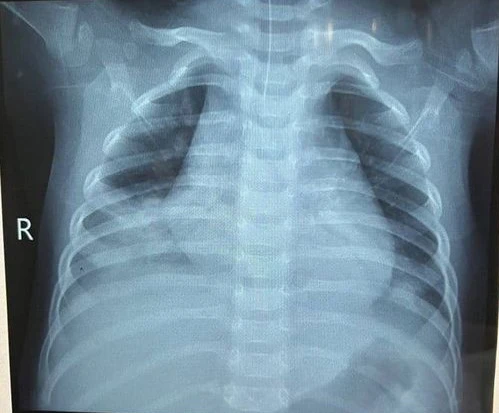

Phim chụp phổi bé trai 14 tháng tuổi nguy kịch sau khi uống dầu hỏa. Ảnh: BVCC

3 ngày trước, bệnh nhi được đưa đến bệnh viện cấp cứu trong tình trạng tím tái, khó thở, nguy kịch. Các bác sĩ đã nhanh chóng hỗ trợ hô hấp bằng máy áp lực cao cho bệnh nhi kết hợp dùng kháng sinh phổ rộng.

Theo bác sĩ Hà Thị Phượng, Trưởng khoa Hồi sức cấp cứu, Bệnh viện Sản Nhi Hưng Yên, ngộ độc do uống nhầm hóa chất rất dễ xảy ra ở trẻ em. Các trường hợp uống dầu hỏa, xăng có thể gây viêm phổi bởi bệnh nhân dễ hít phải hơi độc của hóa chất.